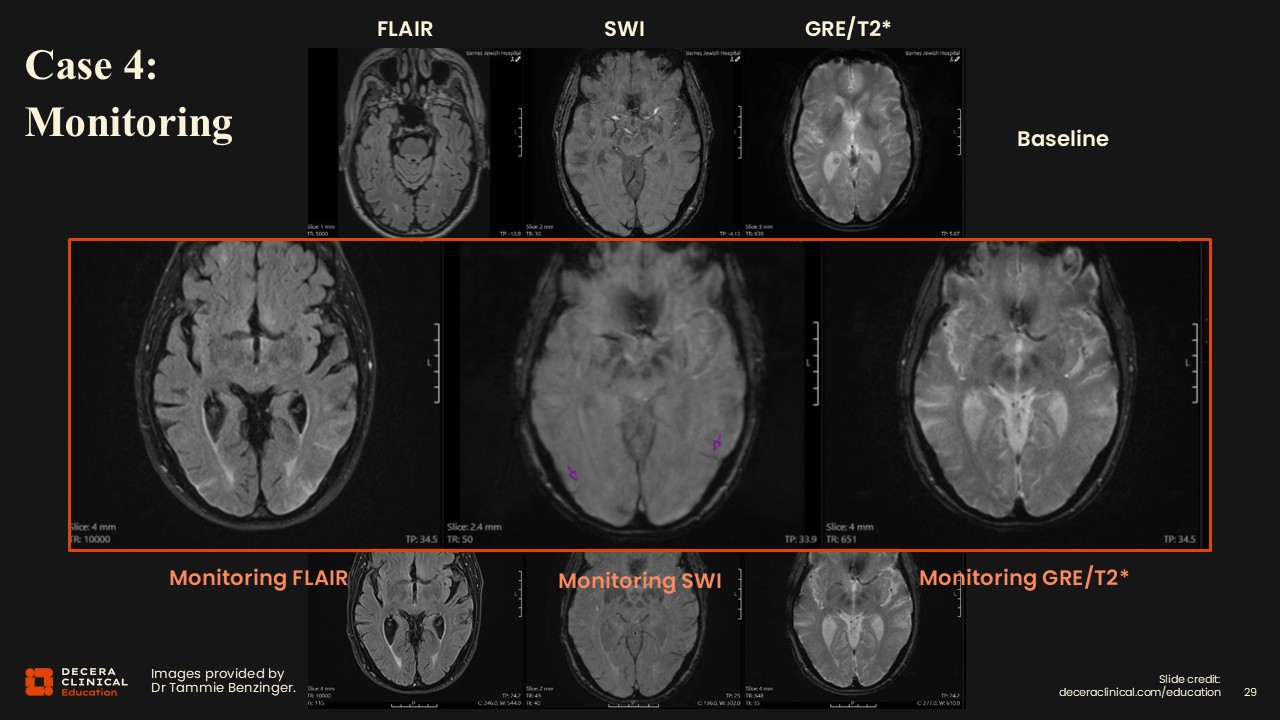

Case 4: Moderate ARIA-E and ARIA-H

Dr Benzinger:

This is a nice example of edema and effusions on FLAIR having similar findings on SWI for siderosis.

Case 4: Moderate ARIA-E and ARIA-H (Detail)

Purple arrows in the inset images show areas of interest; again, the 2 findings occur in the same brain regions.

Case 4: Moderate ARIA-E and ARIA-H (Grading)

Classification for ARIA-E will be moderate because there were 2 different regions less than 10 cm each. For ARIA-H, there were 2 regions of siderosis, so that classification is moderate as well. Our actions would include notifying the clinical team, documenting the grading in our report, and recommending a follow-up MRI for stabilization vs progression. The clinical team will correlate symptoms and determine whether therapy should be paused under the treatment algorithm. Once a case falls into the moderate range, therapy would typically be paused until ARIA resolves/stabilizes.